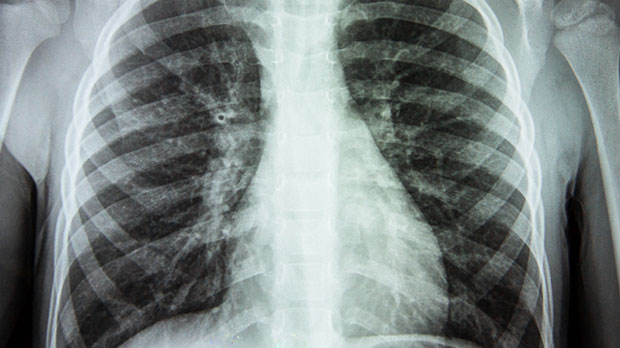

As smoking rates decline in many parts of the world, the proportion of lung cancer cases in non-smokers appears to be increasing. Research from cancer registries shows that a significant minority of lung-cancer patients have never smoked, and in many of these cases the tumour subtype is adenocarcinoma, which tends to occur in the outer lung areas and among non-smokers. The shift suggests environmental, genetic or other lifestyle factors are now playing a more prominent role.

With non-smoking lung cancer on the rise, the spotlight has shifted to possible alternative causes. These include long-term exposure to air pollution, passive (second-hand) smoke, occupational hazards such as asbestos and chemicals, radon gas, and inherited genetic predispositions. While tobacco still dominates overall risk, the emerging evidence emphasises that lung cancer is not a monolithic disease tied strictly to smoking, and that risk assessment must expand accordingly.